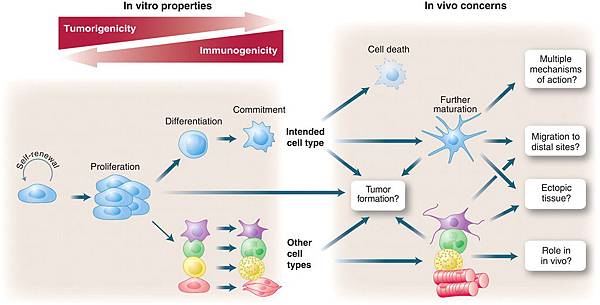

- K. Hochedlinger, Y. Yamada, C. Beard, and R. Jaenisch, “Ectopic expression of Oct-4 blocks progenitor-cell differentiation and causes dysplasia in epithelial tissues,” Cell, vol. 121, no. 3, pp. 465–477, 2005. View at Publisher · View at Google Scholar · View at Scopus

- S. H. Chiou, C. C. Yu, C. Y. Huang et al., “Positive correlations of Oct-4 and Nanog in oral cancer stem-like cells and high-grade oral squamous cell carcinoma,” Clinical Cancer Research, vol. 14, no. 13, pp. 4085–4095, 2008. View at Publisher · View at Google Scholar · View at Scopus

- Y. C. Chen, H. S. Hsu, Y. W. Chen et al., “Oct-4 expression maintained cancer stem-like properties in lung cancer-derived CD133-positive cells,” PLoS One, vol. 3, article e2637, 2008.

- C. Liu, X. Cao, Y. Zhang et al., “Co-expression of Oct-4 and Nestin in human breast cancers,” Molecular Biology Reports, vol. 39, pp. 5875–5881, 2012. View at Publisher · View at Google Scholar

- Y. Guo, S. Liu, P. Wang et al., “Expression profile of embryonic stem cell-associated genes Oct4, Sox2 and Nanog in human gliomas,” Histopathology, vol. 59, pp. 763–775, 2011. View at Publisher · View at Google Scholar

- P. F. Caimi, J. Reese, Z. Lee, and H. M. Lazarus, “Emerging therapeutic approaches for multipotent mesenchymal stromal cells,” Current Opinion in Hematology, vol. 17, no. 6, pp. 505–513, 2010. View at Publisher · View at Google Scholar · View at Scopus